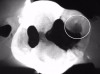

Fig 4. Case 1. Bitewing radiograph shows no indication of caries on tooth No. 14.

Figure 4

Fig 7. Case 2. Bitewing radiograph shows no indication of interproximal or recurrent caries around the composite restoration on tooth No. 13.

Figure 7